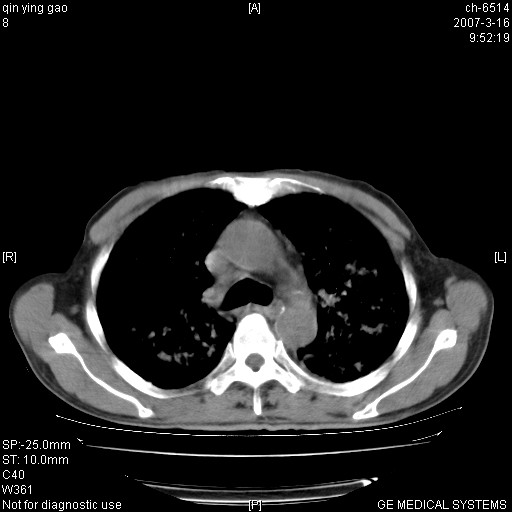

标题: CT7174:两肺弥漫性病变,请讨论

男,64岁.乏力2个月,畏寒、发热1月余。体重下降。血沉加快,白细胞不高。

双肺以中上肺野为著斑片状.结节壮密度增高影 左上肺前段可见小类圆钙化灶 纵隔淋巴结无明显肿大

3.主动脉弓.冠状动脉钙化形成

两肺弥漫分布的斑片状影,部分融合,左肺及纵隔淋巴结见钙化影,考虑1。tb,2。肺泡细胞癌,建议查痰检

病变以两肺上野为著,部分病灶有钙化,纵隔窗显示病灶有新老不一,这个首先和结核脱不了干系,还有部分病灶有融洽的倾向,肿瘤也不能完全排出